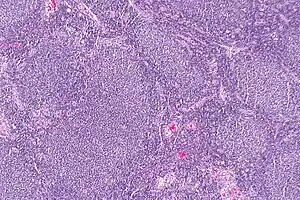

Follicular lymphoma (FL) is a cancer that involves certain types of white blood cells known as lymphocytes. The cancer originates from the uncontrolled division of specific types of B-cells known as centrocytes and centroblasts. These cells normally occupy the follicles (nodular swirls of various types of lymphocytes) in the germinal centers of lymphoid tissues such as lymph nodes. The cancerous cells in FL typically form follicular or follicle-like structures (see adjacent Figure) in the tissues they invade. These structures are usually the dominant histological feature of this cancer.[1]

| Micrograph of a follicular lymphoma, showing the characteristically abnormal lymphoid follicles that gave the condition its name. H&E stain. | |

The diagnosis of FL depends on examining involved tissues for histological, immunological, and chromosomal abnormalities that are indicative of the disease. FL usually involves enlarged lymph nodes populated by abnormal follicles (see adjacent picture) that when examined histologically contain a mixture of centrocytes or centroblast surrounded by non-malignant cells, mostly T-cells. The centrocytes, which typically outnumber centroblasts, are small to medium-sized B-cell lymphocytes that characteristically exhibit cleaved nuclei; the centropblasts are larger B-cell lymphocytes without cleaved nuclei.[11] Rare cases of FL may show lesions that contain tissue infiltrations dominated by B-cells with features of precursor (i.e. "blast") cells, monocytes, or malignant mantle cells such as those found in mantle cell lymphoma.[1] Immunochemical analyses reveal that these cells generally express B-cell surface markers including the CD10 (60% of cases), CD20, CD19, CD22, and CD79 but not CD5, CD11c, or CD23 cell surface proteins;[4] genomic analyses reveal that these cells contain t(14:18)(q32:q21.3) translocation (85–90% of cases), 1p36 deletions (60–70% of cases), and with far less frequency the other genomic abnormalities listed in the above sections on Pathophysiology and Presentation and course. None of these protein markers or genomic abnormalities are diagnostic for FL, e.g. the t(14:18)(q32:q21.3) translocation is found in 30% of diffuse large B-cell lymphoma and in a small number of reactive benign lymph nodes. Rather, the diagnosis is made by a combination of histological, immunological, and genomic abnormalities.[4] According to World Health Organization (WHO) criteria, follicular lymphoma can be classified morphologically by the relative amount of centroblasts. However, such classification is optional, due to poor reproducibility and little difference in prognosis and treatment, except that a lymphoma with almost only centroblasts may be diagnosed as a diffuse large B-cell lymphoma (DLBCL).[50] The optional classification of follicular lymphoma is as follows:[51]